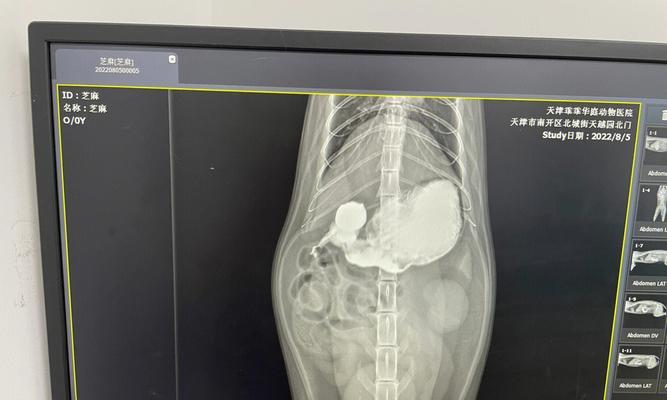

1.了解钡餐的意义:钡餐是一种医学检查方法,通过口服含有钡剂的液体或食物,配合X光检查消化道情况。它有助于诊断和治疗猫咪的消化道问题。